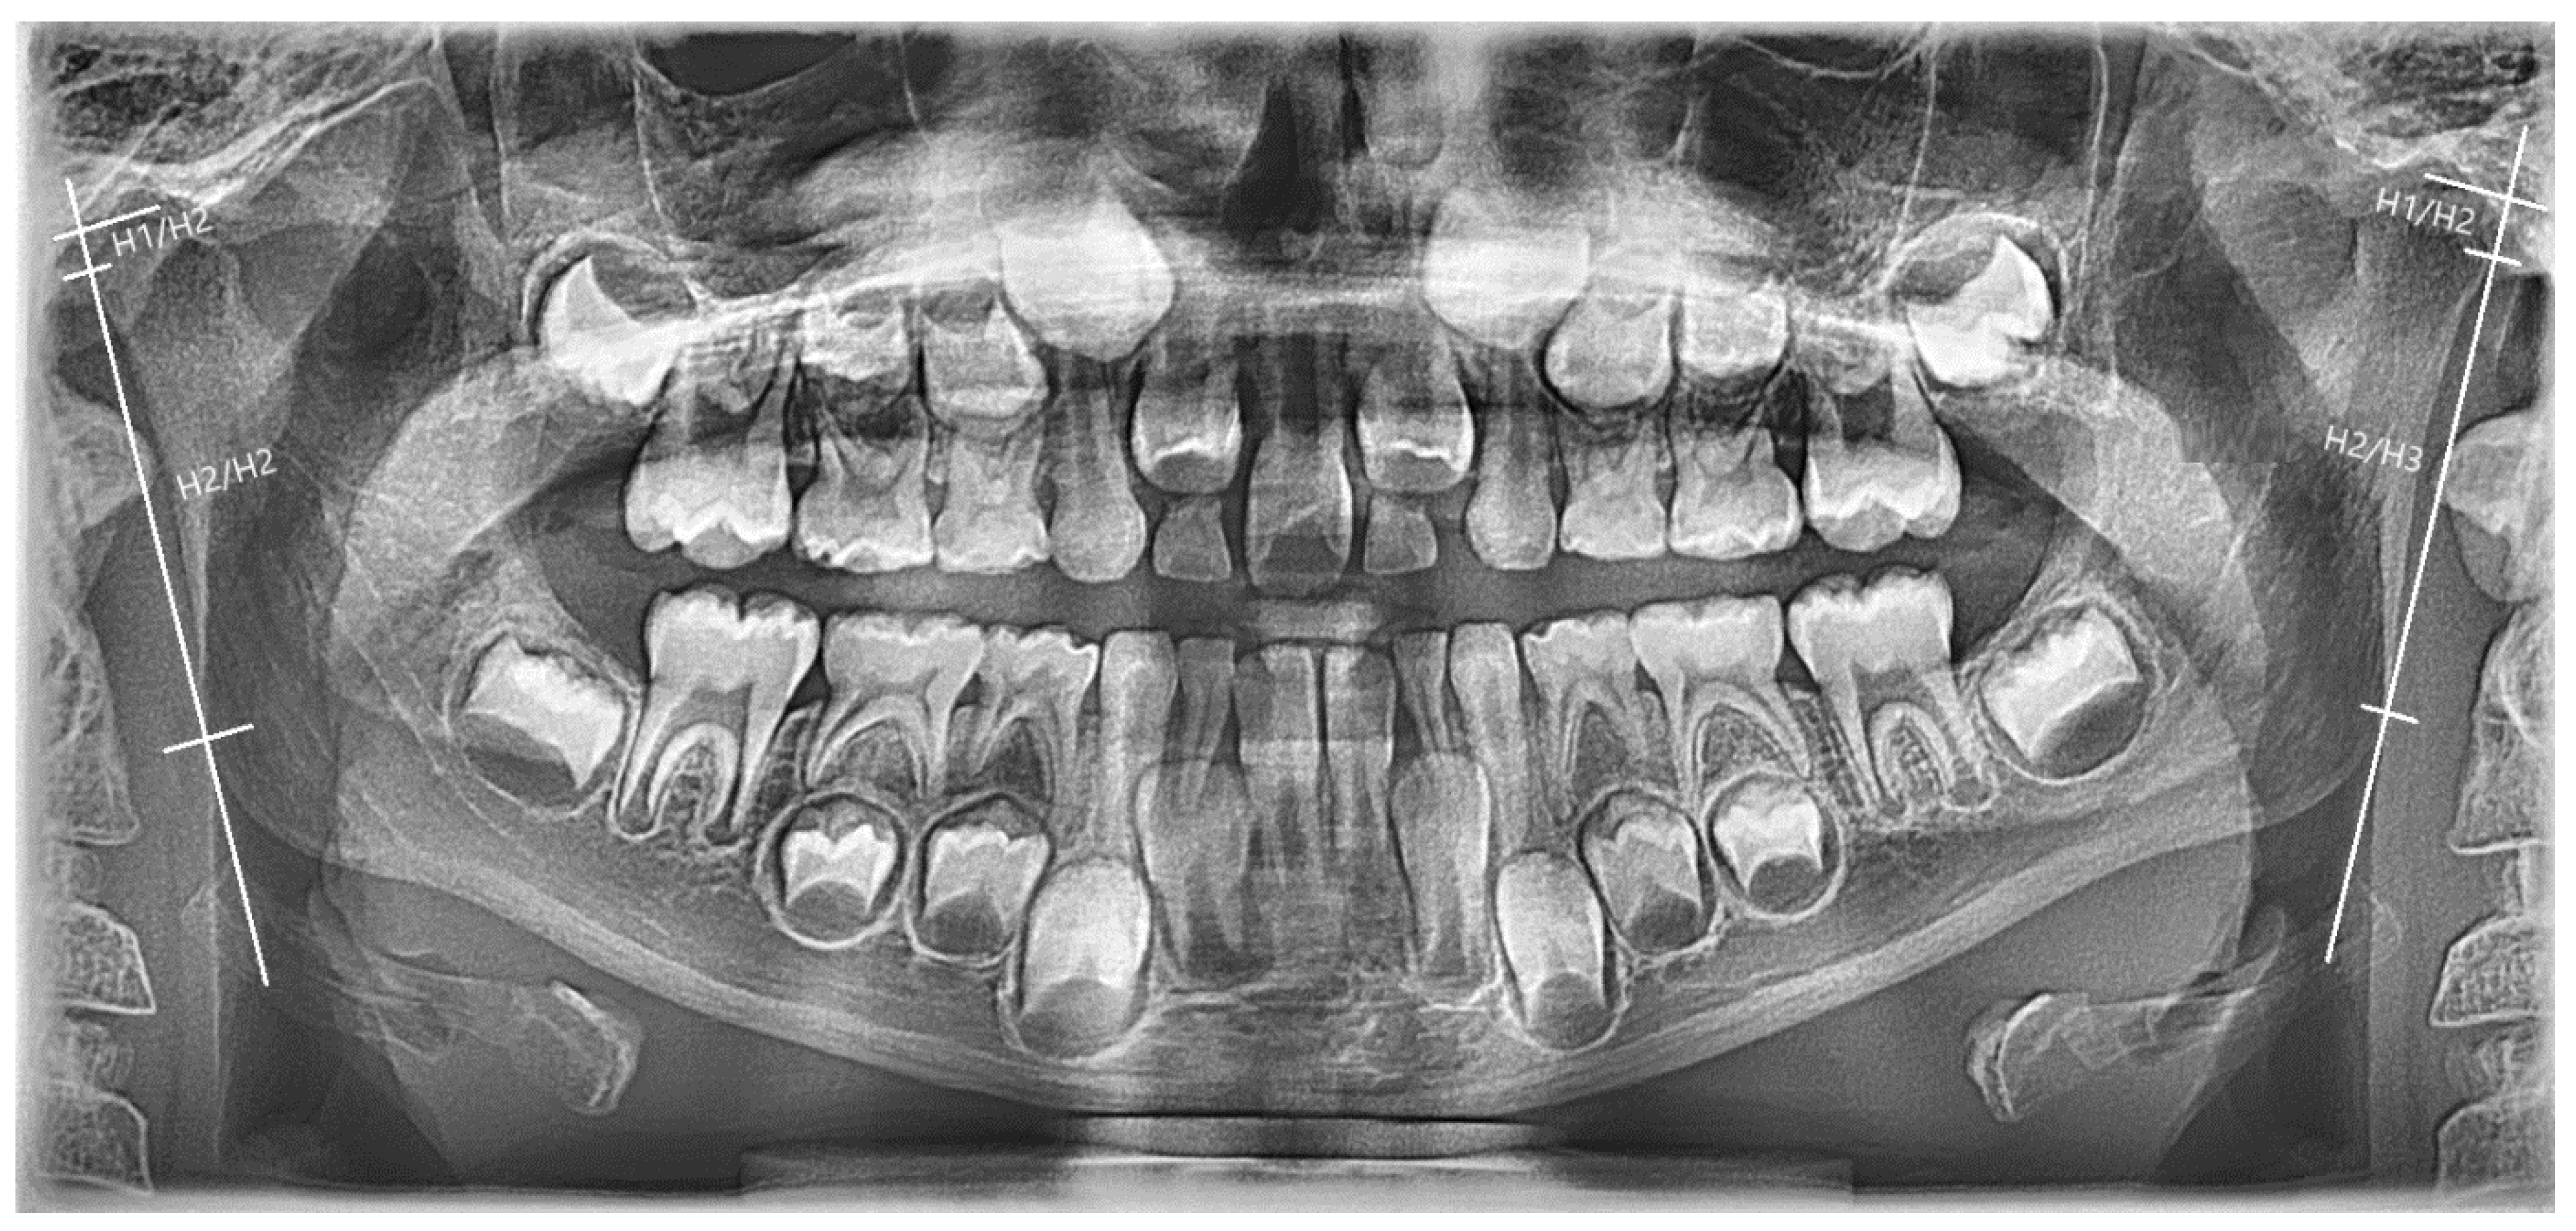

Case Description